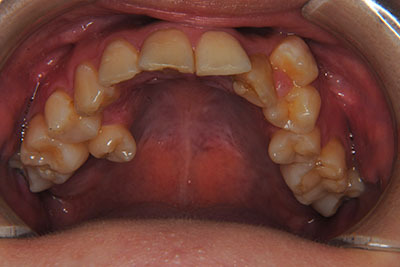

お口の中を診ますと、左上第二小臼歯が歯列の内側に生え、左上犬歯のスペースは全くない八重歯となっていました。検査結果から骨格的な不正はなく。上奥歯が前にずれたかみ合わせで前歯は合っていて出っ歯ではないので左右1本ずつ歯列からはみ出した状態であることがわかりました。上の奥歯を横の歯1本分後ろにずらすことは困難なので、右上中側に生えている第二小臼歯と八重歯である左上犬歯の次の歯=第一小臼歯の2本を抜歯し治療しました。